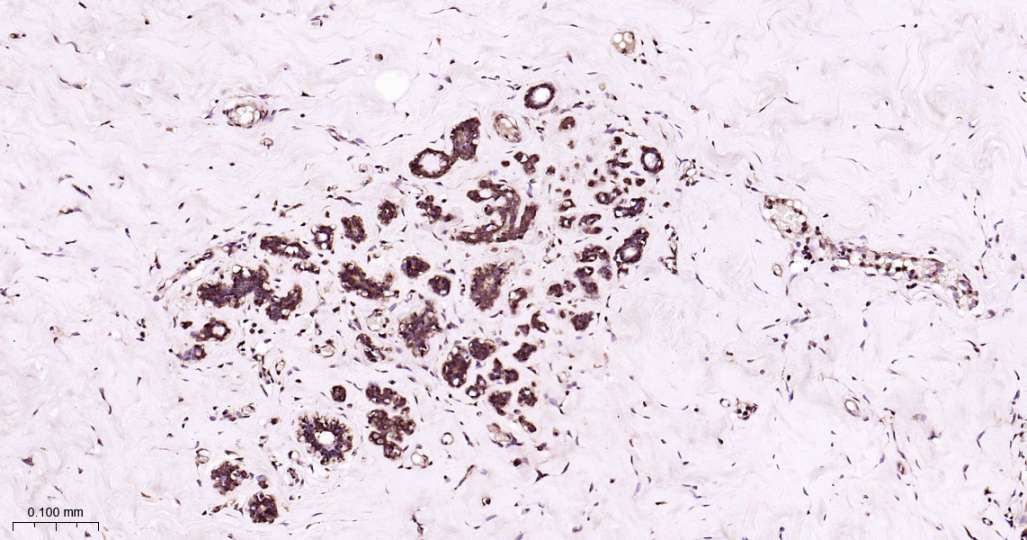

Immunohistochemical analysis of paraffin embedded Human breast cancer tissue slide using IHC0603H (Human PSMA1 Kit).

Immunohistochemical analysis of paraffin embedded Human mammary gland tissue slide using IHC0603H (Human PSMA1 Kit).